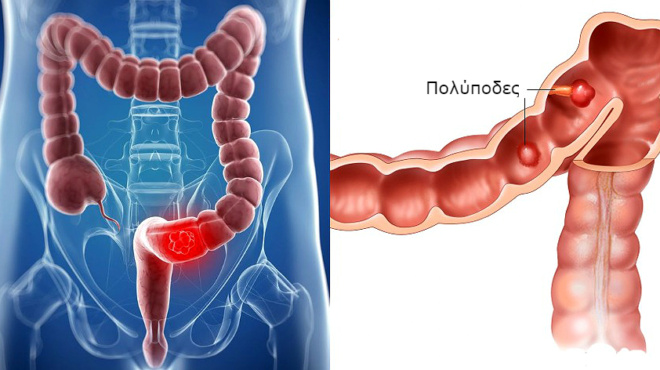

Ορισμένες μορφές καρκίνου αυξάνουν την ποσότητα των ουσιών στο αίμα σας που το κάνουν να πήζει. Ορισμένες μορφές θεραπείας του καρκίνου αυξάνουν επίσης τον κίνδυνο θρόμβωσης του αίματος.

Φλεγμονώδης νόσος του εντέρου

Ασθένειες του εντέρου, όπως η νόσος του Crohn (κοιλιοκάκη), ή η ελκώδης κολίτιδα, αυξάνουν τον κίνδυνο της ΕΒΦΘ.